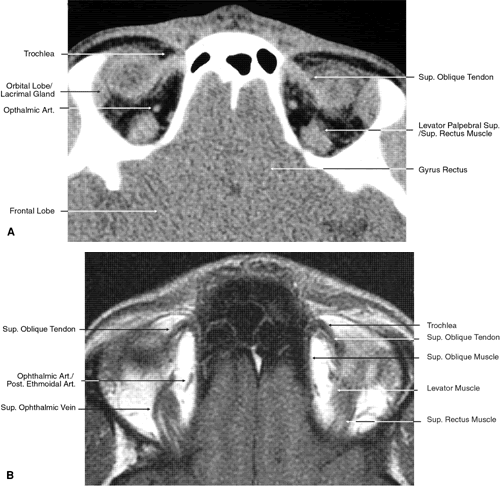

The globe is shown in Figure 12. The orbit and periorbital structures are shown in Figures 13 through 16, and the optic canal is shown in Figures 17 through 26. The cavernous sinus and optic chiasm are shown in Figures 27 and 28, and the posterior visual pathway and cranial nerves are shown in Figures 29 through 33.

Fig. 18. Coronal images through midglobe. A. Computed tomography scan. B. T1-weighted magnetic resonance imaging.

Fig. 19. Coronal images through midorbit posterior to the globe. A. Computed tomography scan.B. T1-weighted magnetic resonance imaging.

Fig. 20. Coronal images through orbital apex. A. Computed tomography scan. B. T1-weighted magnetic resonance imaging. C. Anatomic section of a cadaver head at the level of the orbital apex.